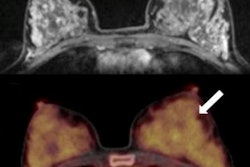

In addition, before biopsy, subjects also underwent 1.5-tesla breast MRI scans, with the dedicated breast PET exam following. The researchers then fused MRI and dedicated breast PET images to better locate corresponding lesions and to avoid misinterpretation of dedicated breast PET results.

Dedicated breast PET discovered 19 lesions; 10 were benign and nine were malignant. However, the modality missed a significant number of carcinomas in situ and approximately one-fourth of invasive cancers. In other words, there were nine (50%) false-negative results in the sample.